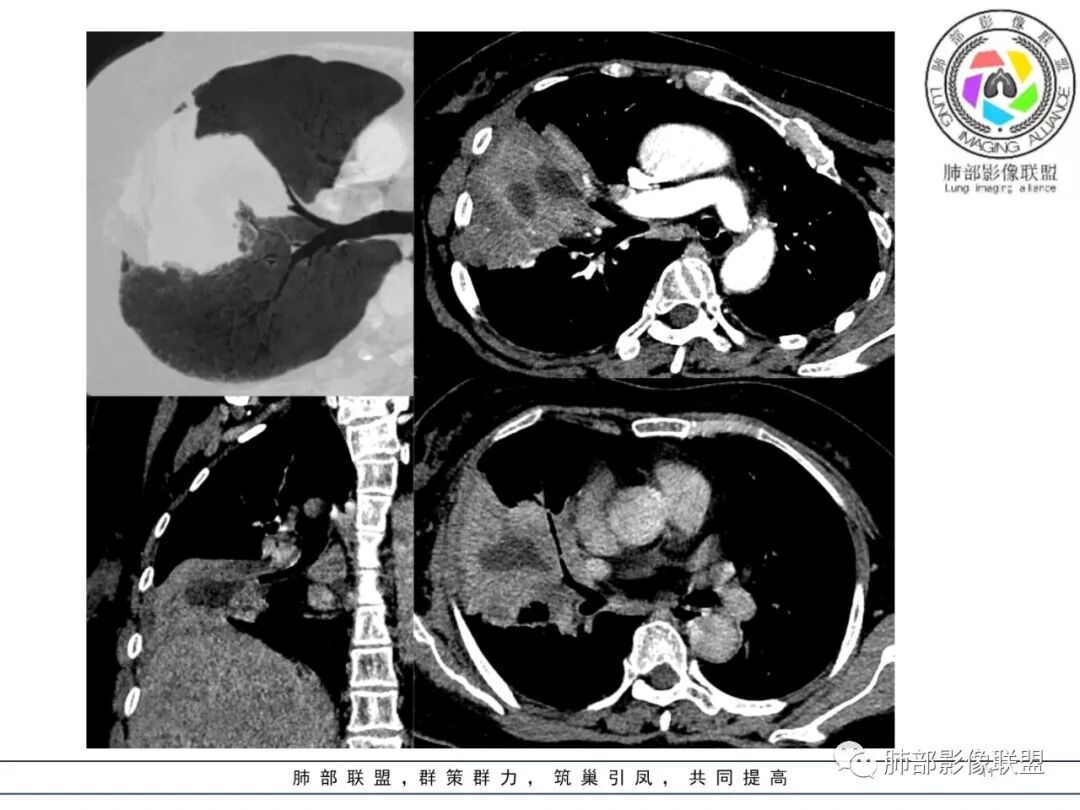

这个病例,看长轴、形态,首先跨叶,里面的坏死腔,它是相通的,就是跨中叶及前基底段。

看中叶外侧段的病变,我观察到支气管与坏死腔相通的,支气管这种堵塞就不踏实了,假如是腔内的病变,就不太支持。

如果是腔内的病变,第一,应该是局限在某个叶的,不可能上下叶都有。所以不太支持腔内的病变。因此考虑腔外的病变。腔外局限的肿瘤肯定不符合,假如这个病灶是个局限大肿块的话,里面肺动脉走势还可以。

然后中叶与下叶的坏死腔病灶是相通的,病灶是跨叶的,胸膜糊墙为主。

我要看一下下叶。还想重建一下,就是按照我自己理解的长轴去重建出这个病灶的整体形态,我当时一看,好像侧向融合的病灶。侧向融合的病灶考虑慢性炎性病变的,有几种,这样大片的病灶,常规都考虑特殊感染多一些,比如隐球,放线菌,奴卡等,都可以这样的改变。

现有的CT,里面存在坏死腔。炎症肯定有,是否同时合并肿瘤的问题?我需要详细的图将内部结构逐步剖析出来,看看能否有新的依据

南边:跨叶、楔形/边缘平直、支气管壁无破坏/连续/局部无膨大、实变区肺动脉走形自然、实性部分均匀、延迟强化、坏死腔内壁光滑/内壁强化环/近端与支气管相通,这些点均支持炎性。所以综合分析:符合炎性。